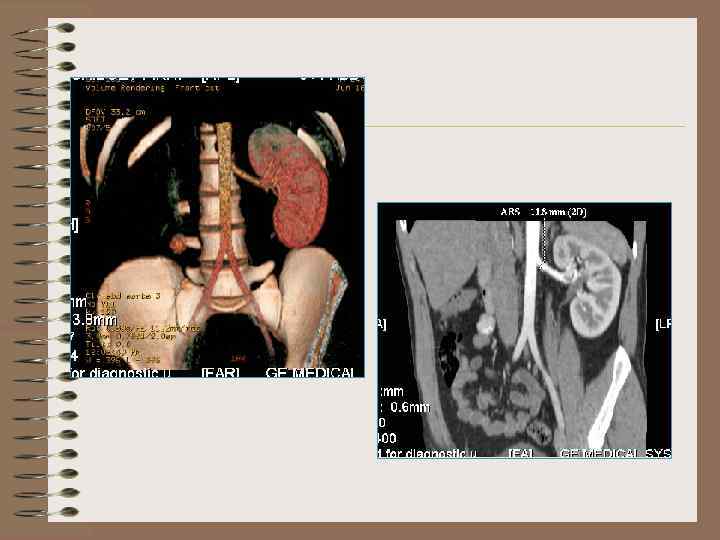

ВУ, КТ – тазовая дистопия

КТ – подковообразная почка Нативная Контрастирование выделительная фаза

КТ- подковообразная почка.